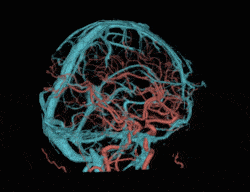

AI冠脉追焦

基于AI技术,对搏动的冠脉进行精准的识别、追踪、运动建模和运动伪影校正